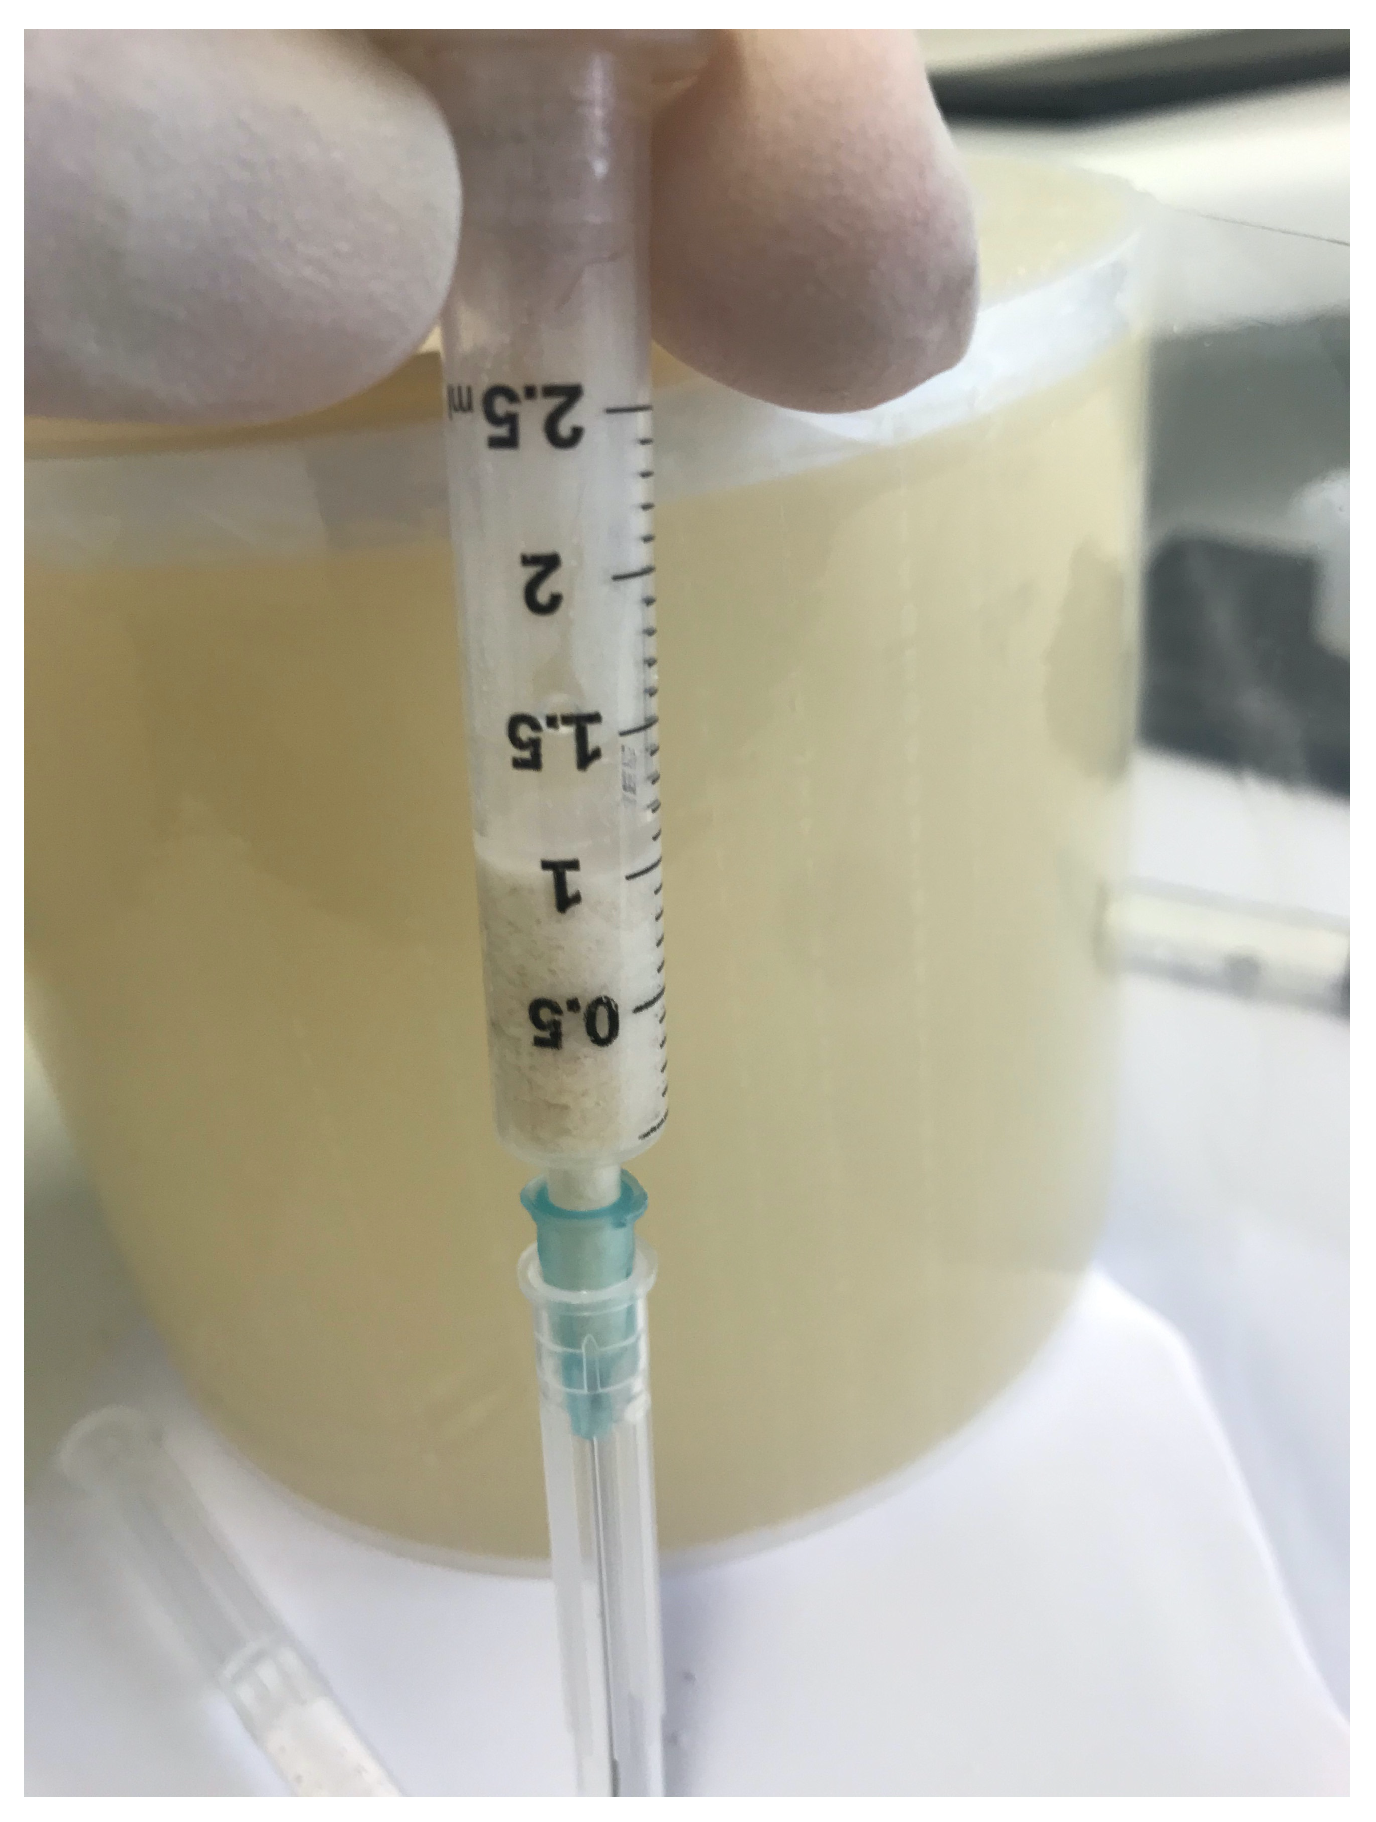

2.4. Surgical Procedures and Follow-Up

- Minetti, E.; Berardini, M.; Trisi, P. A New Tooth Processing Apparatus Allowing to Obtain Dentin Grafts for Bone Augmentation: The Tooth Transformer. Open Dent. J. 2019, 13, 6–14. [Google Scholar] [CrossRef]